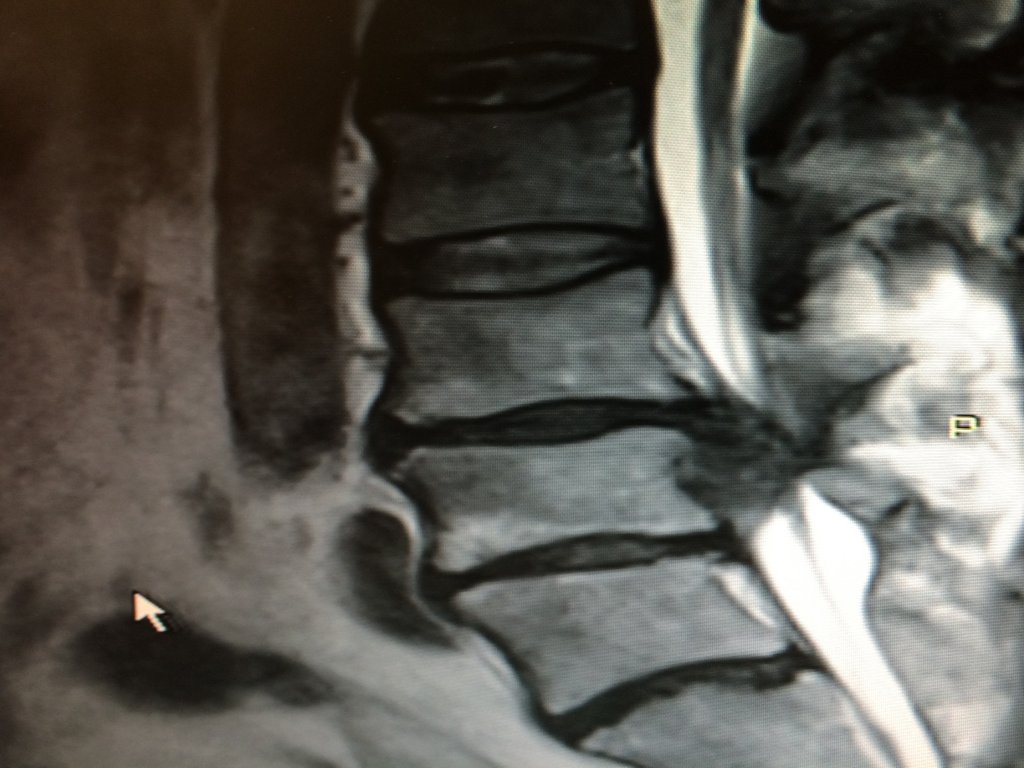

dyskopatia lędźwiowa MRI

Dyskopatia lędźwiowa - obraz rezonansu magnetycznego